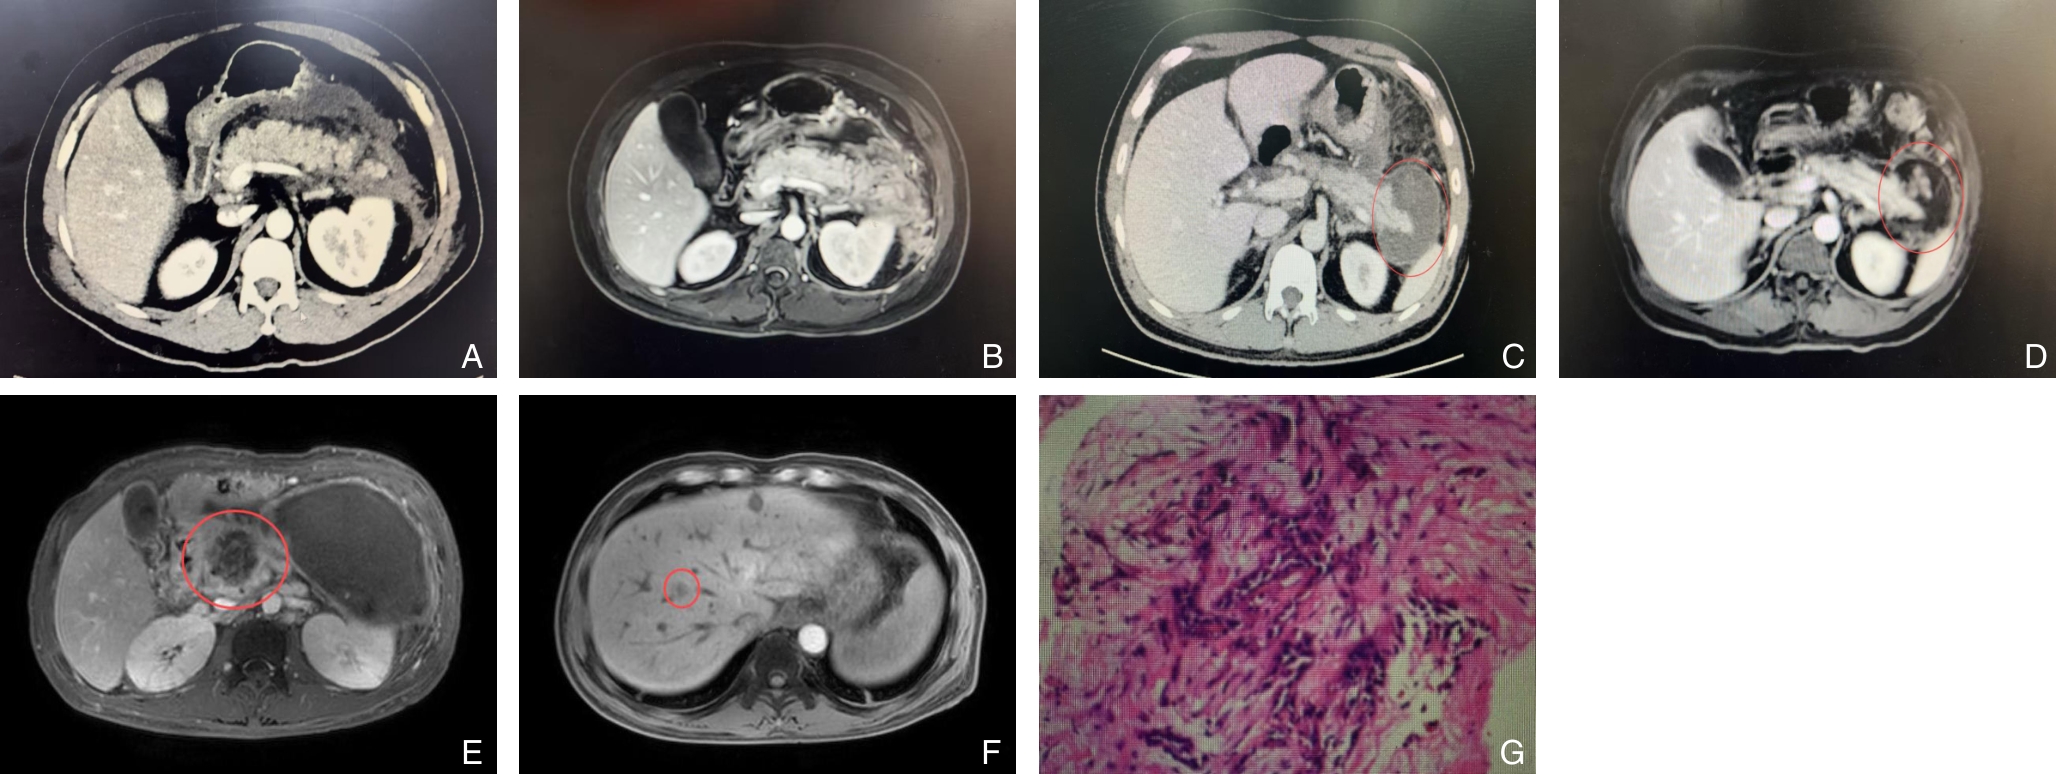

摘要:背景与目的 急性胰腺炎(AP)是一种由多种因素引起的胰腺急性炎症反应,以胰酶异常激活及自身消化为主要特征。尽管常见病因为胆石症、高脂血症及饮酒,但部分患者的病因罕见且诊断延迟,易导致复发及误治。本文通过分析4例以AP为首发症状的少见病因病例,并结合文献复习,总结其诊断思路与治疗经验,为临床鉴别诊治提供参考。方法 回顾性分析中南大学湘雅三医院2021年11月—2024年9月收治的4例以AP为首发表现的少见病因患者的临床资料,结合国内外相关文献,探讨其病因特征、诊断要点及治疗策略。结果 4例患者的病因为胰腺导管内乳头状黏液性肿瘤、胰腺神经内分泌瘤、胰腺癌及十二指肠肠套叠。所有病例初诊时均表现为不明原因AP。经系统评估后,3例患者接受手术根治,术后恢复良好;1例患者因胰腺癌确诊较晚,仅行姑息性治疗,3个月后死亡。结论 少见病因所致的AP临床表现与常见类型相似,早期识别难度大。针对反复发作或原因不明的AP,应重视病因追溯,充分利用影像学及内镜检查手段明确诊断。对可手术病变应积极干预,以减少复发并改善预后。

刘勐,王恒,孔晓晗,杨发基,牛哲禹,郝以杰,王新,朱化强,高恒军,卢俊,周旭